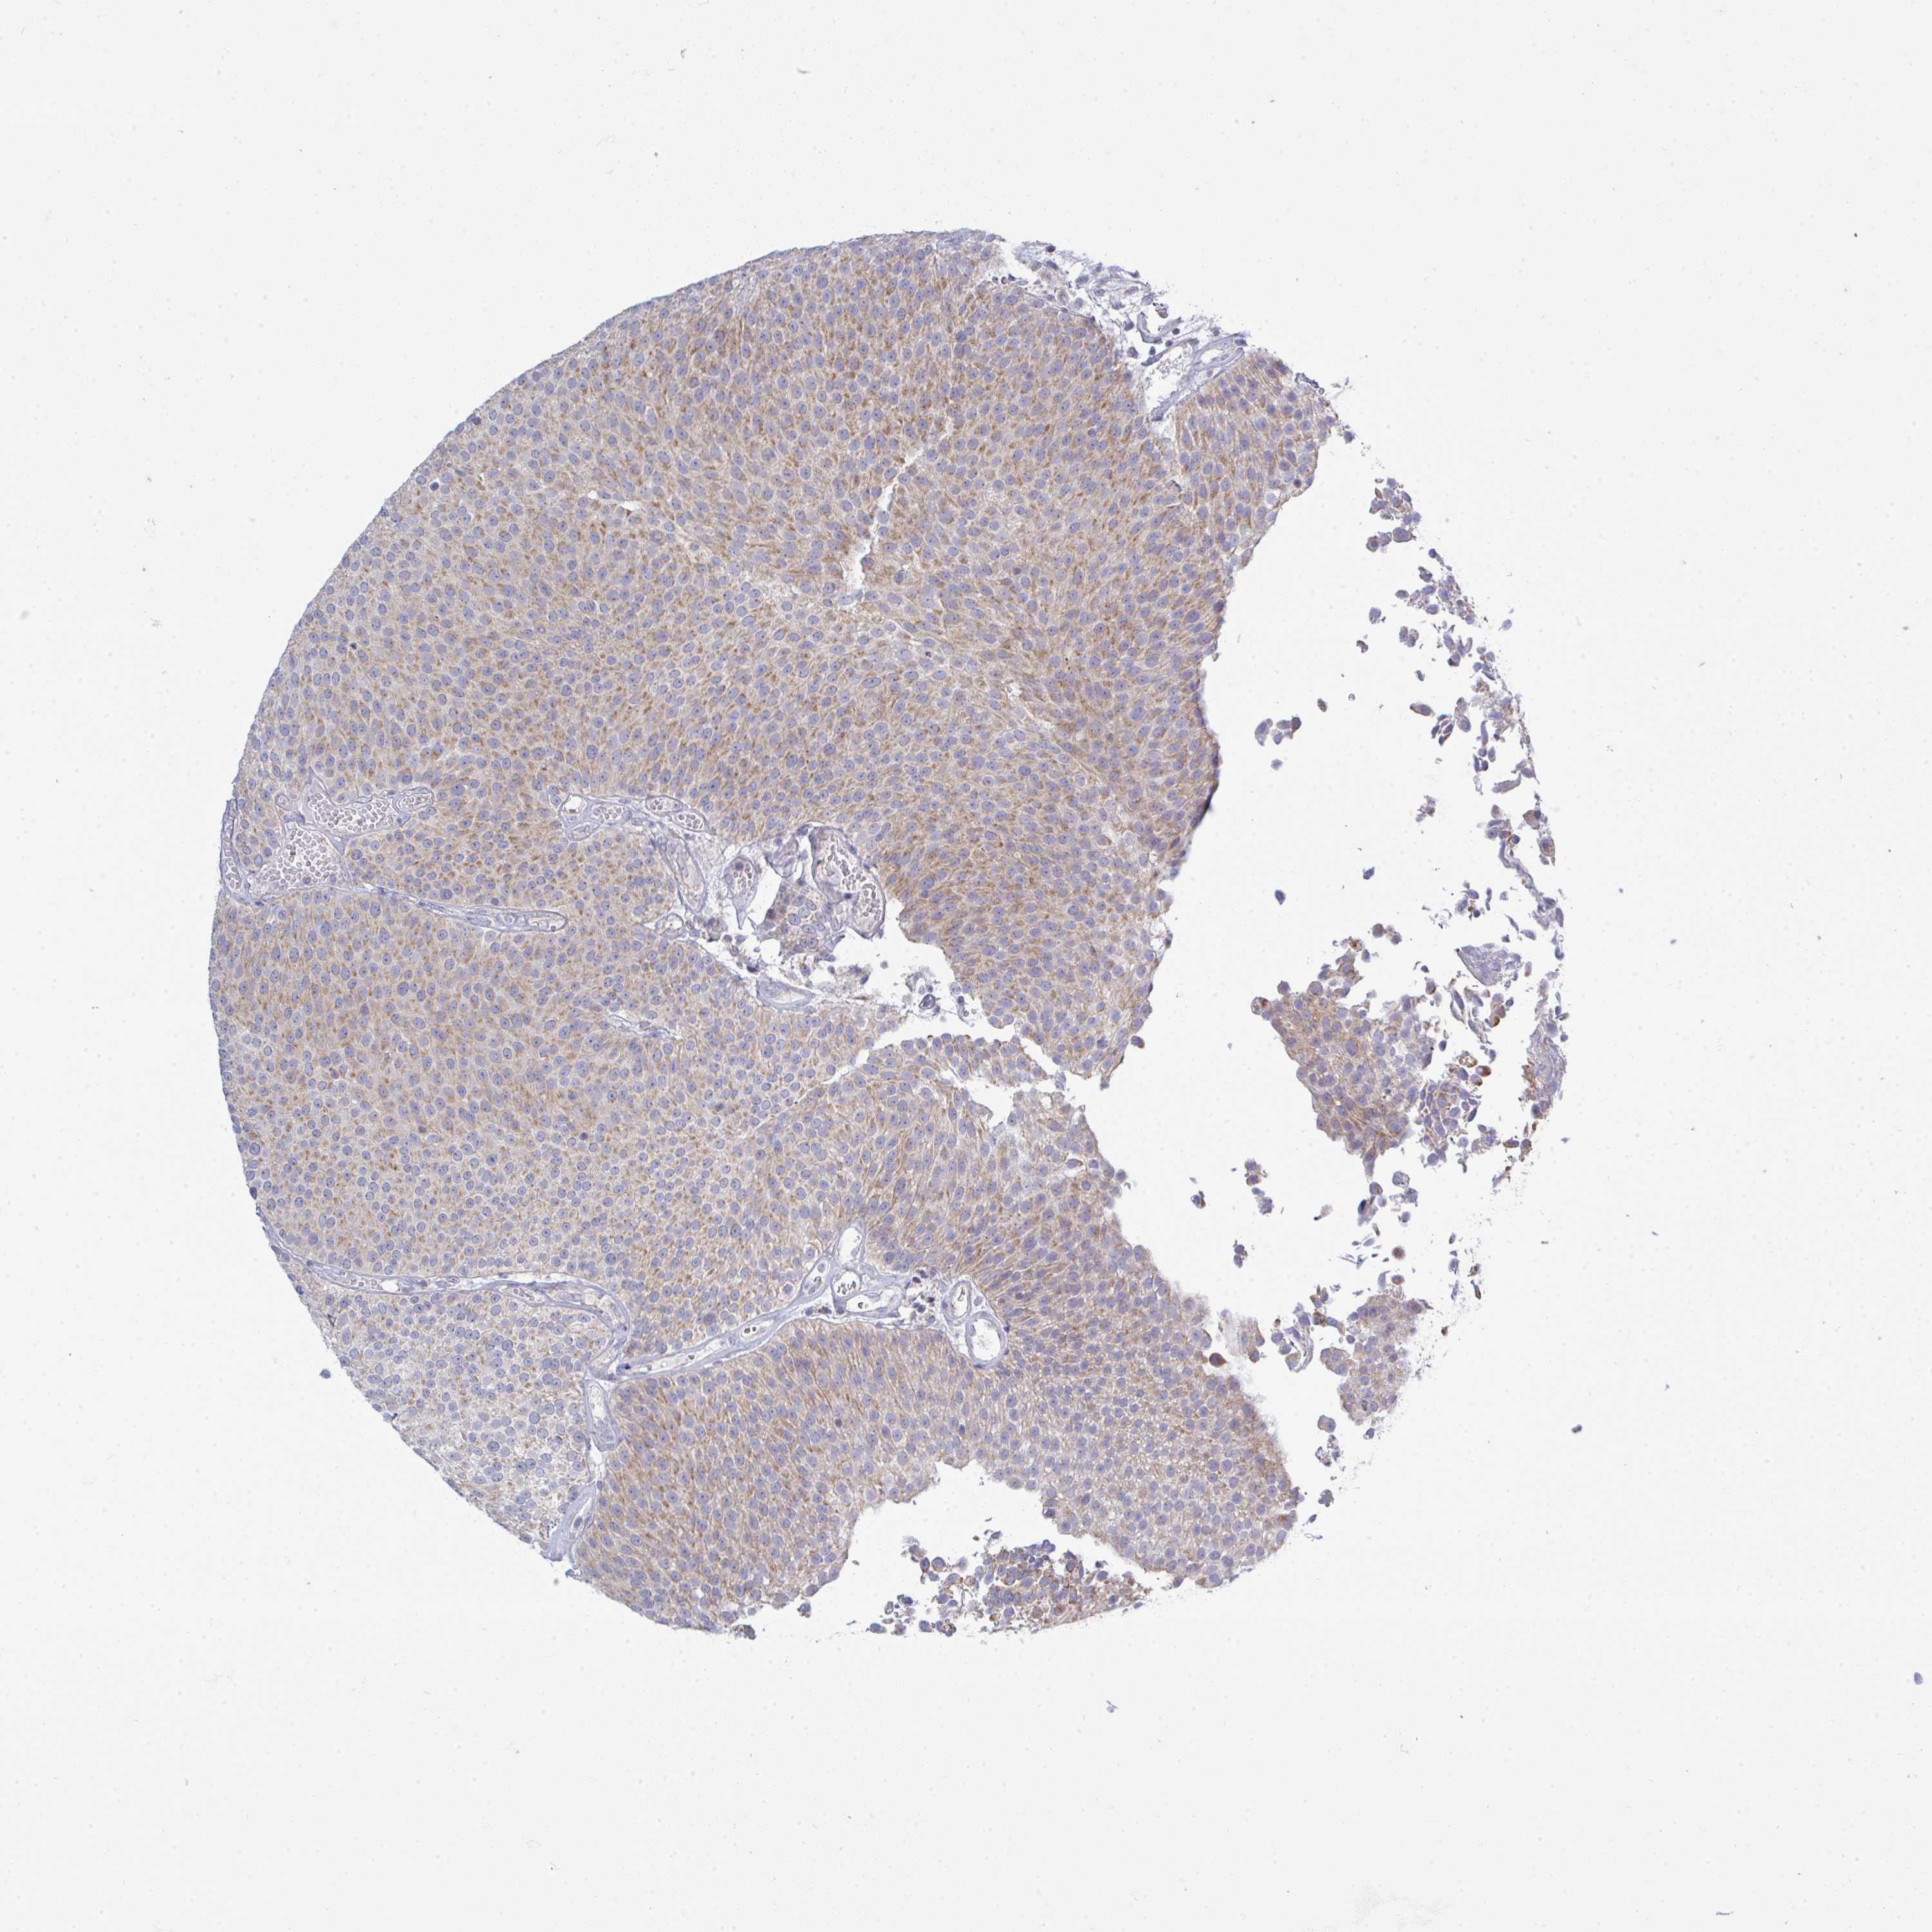

UROTHELIAL CANCER - Protein expressioni

A mouse-over function shows sample information and annotation data. Click on an image to view it in a full screen mode. Samples can be filtered based on level of antibody staining by selecting one or several of the following categories: high, medium, low and not detected. The assay and annotation is described here.

Note that samples used for immunohistochemistry by the Human Protein Atlas do not correspond to samples in the TCGA dataset.

Antibody stainingi

Antibody staining in the annotated cell types in the current human tissue is reported as not detected, low, medium, or high, based on conventional immunohistochemistry profiling in selected tissues. This score is based on the combination of the staining intensity and fraction of stained cells.

Each image is clickable and will lead to virtual microscopy that enables deeper exploration of all samples and also displays staining intensity scores, fraction scores and subcellular localization as well as patient and tissue information for each sample.

Antibody HPA059251

Antibody HPA071866

Urothelial carcinoma, High grade

Urothelial carcinoma, Low grade

Urothelial carcinoma, NOS